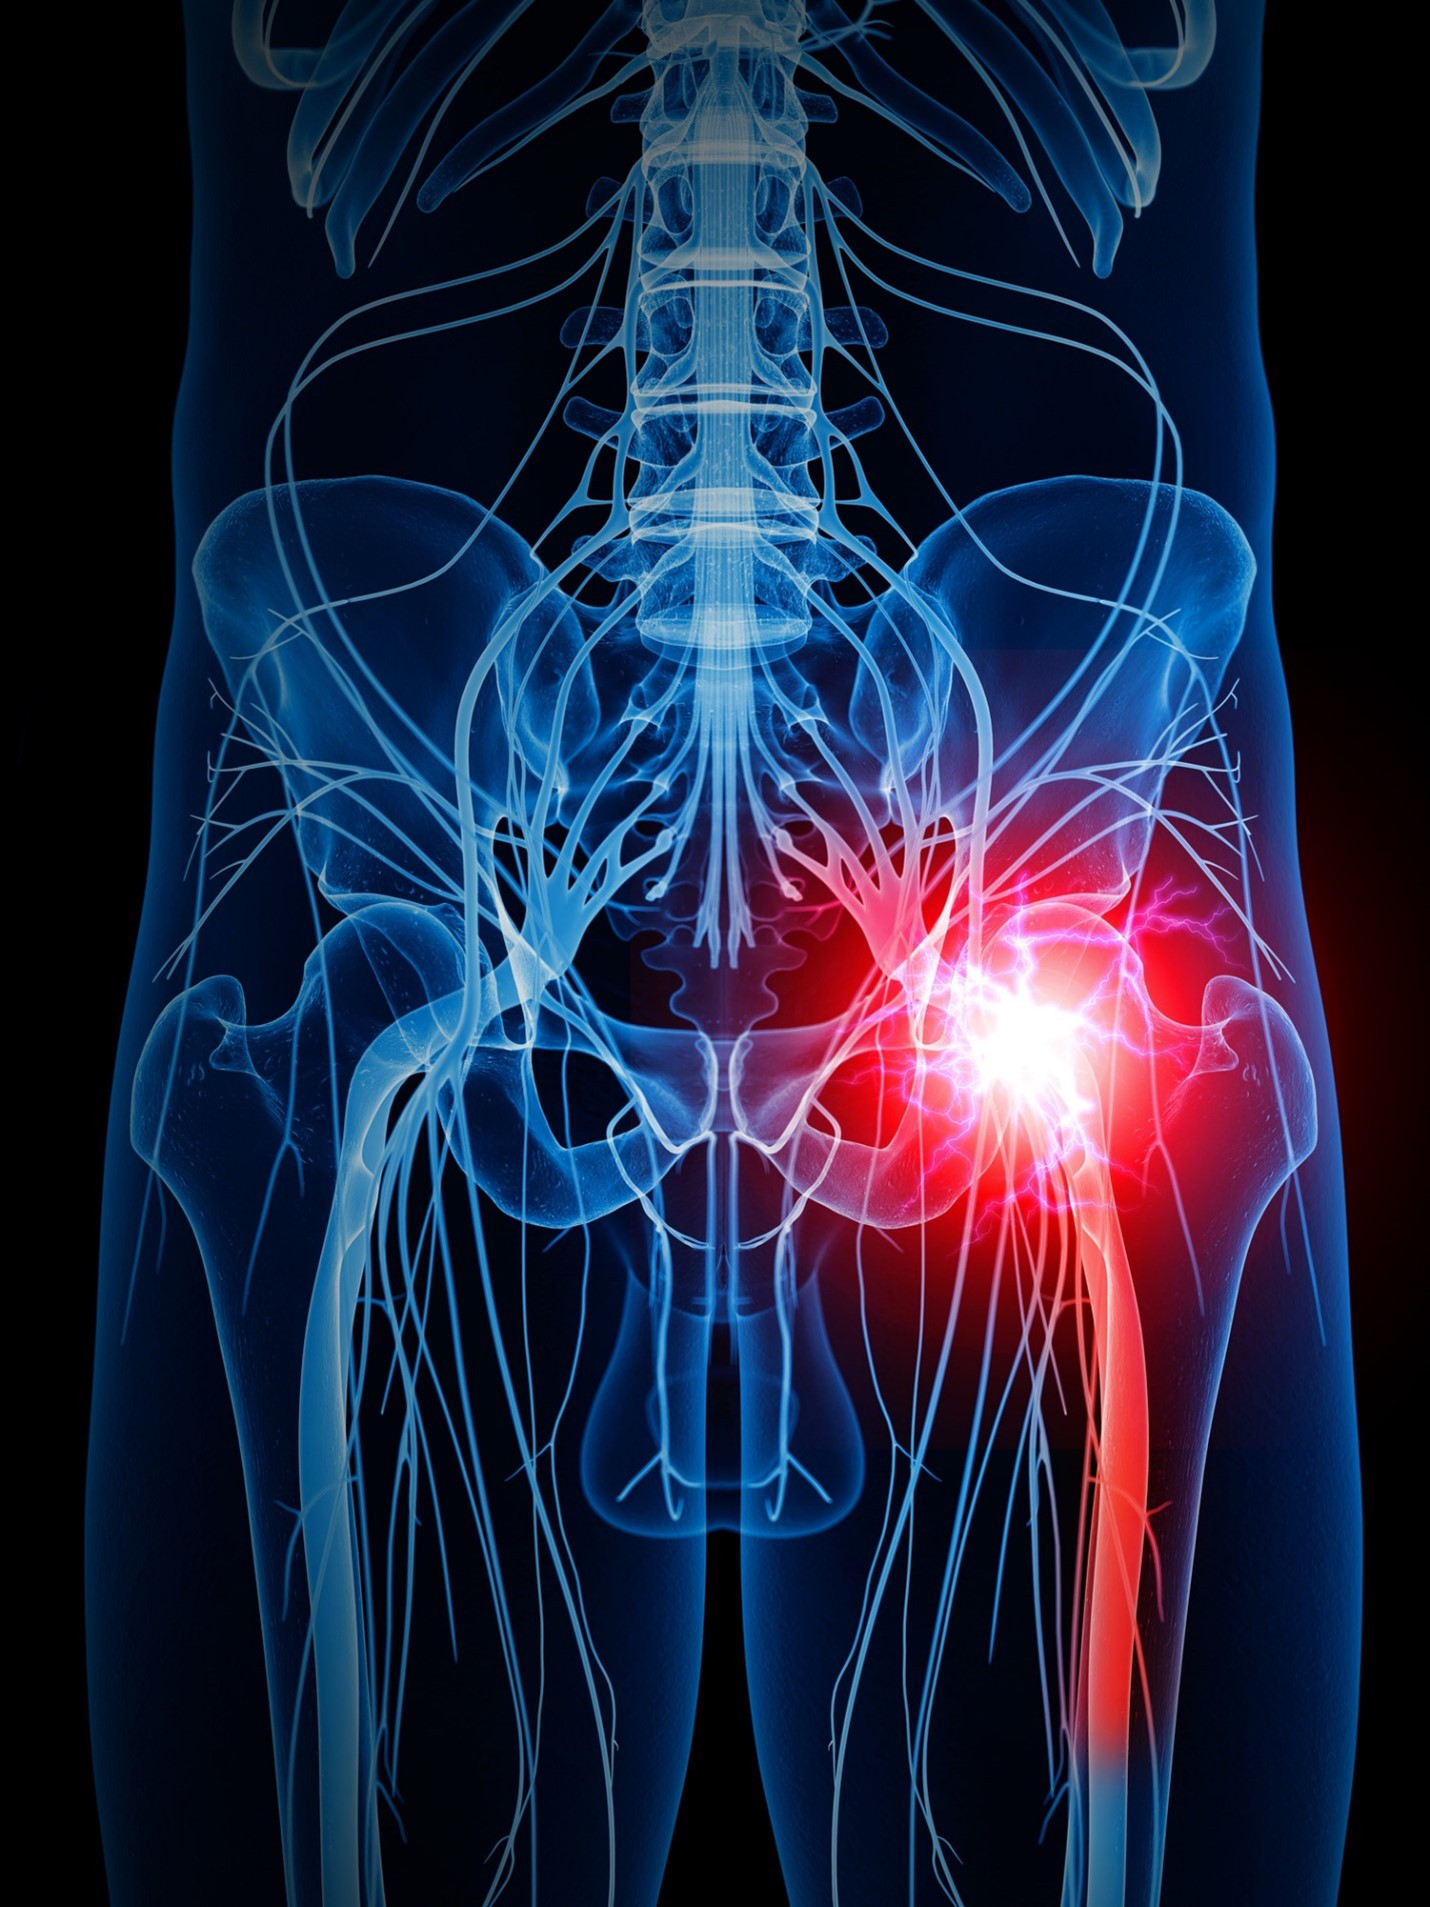

Understanding Sciatica

Sciatica is a common condition; it causes pain that radiates along the path of the sciatic nerve which runs from the lower back through the hips and buttocks and down each leg. Sciatica typically occurs when the sciatic nerve is compressed or irritated. Common causes include:

Recognizing Sciatica Symptoms

Symptoms of sciatica can vary but commonly include:

- Pain: Sharp or burning pain that radiates from the lower back down the leg. Symptoms may worsen with prolonged sitting, standing, or sudden movements.

- Numbness or Tingling: A feeling of pins and needles in the leg or foot.

- Weakness: Difficulty moving the affected leg or foot.